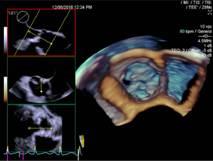

自贡市第四人民医院超声医学科自今年6月开展自贡市首例局部麻醉下经食道超声心动图检查以来,近日,该科又率先在川南开展了局部麻醉下经食道四维超声心动图检查。

患者袁先生,有心脏二尖瓣及主动脉瓣杂音。心血管内科医生怀疑二尖瓣和主动脉瓣瓣膜病。12月5日早上,在超声室行局部麻醉下经食道四维超声心动图检查,清晰显示主动脉瓣重度狭窄,钙化呈功能二叶,排除了二尖瓣瓣膜病变,给临床提供了依据。